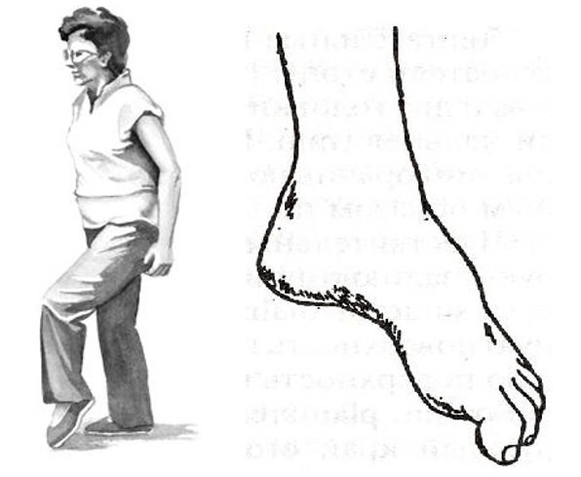

Çoğu zaman, bu tür bozukluklar bacaklarda, lomber omurganın çıkıntıları ve fıtıkları ile birlikte görülür. Alt bacak ve ayak kaslarını innerve eden motor yapılar bulunur. Bu nedenle, ilerlemiş, karmaşık lomber osteokondrozda ayak şaplak atabilir. İçe doğru döner, kişi şaplak atan ayakla adım atmak için bacağını yukarı kaldırmak zorunda kalır, buna steppage, "horoz yürüyüşü" denir.

Ancak hareket bozukluklarının tüm tehlikesi, izole edilebilmeleri ve ağrıya eşlik etmemeleridir. Ve eğer bir kişinin "ağrısı yoksa" zamanında doktora gidemeyebilir. Bu nedenle, örneğin bel bölgesinde ilerleyici çıkıntılar ve fıtıklar olan hastaların periyodik olarak ayak parmakları ve topuklar üzerinde yürümeleri, kaslarının çalışmalarını izlemeleri çok önemlidir.